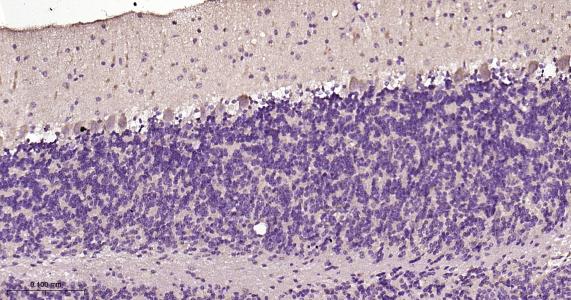

Paraformaldehyde-fixed, paraffin embedded Rat Cerebellum; Antigen retrieval by boiling in sodium citrate buffer (pH6.0) for 15 min; Antibody incubation LC3B Monoclonal Antibody, Unconjugated(bsm-60842R) at 1:200 overnight at 4°C, followed by conjugation to the bs-0295G-HRP and DAB (C-0010) staining.

Paraformaldehyde-fixed, paraffin embedded Mouse Cerebellum; Antigen retrieval by boiling in sodium citrate buffer (pH6.0) for 15 min; Antibody incubation LC3B Monoclonal Antibody, Unconjugated(bsm-60842R) at 1:200 overnight at 4°C, followed by conjugation to the bs-0295G-HRP and DAB (C-0010) staining.

Paraformaldehyde-fixed, paraffin embedded Rat Cerebrum; Antigen retrieval by boiling in sodium citrate buffer (pH6.0) for 15 min; Antibody incubation LC3B Monoclonal Antibody, Unconjugated(bsm-60842R) at 1:200 overnight at 4°C, followed by conjugation to the bs-0295G-HRP and DAB (C-0010) staining.

Paraformaldehyde-fixed, paraffin embedded Mouse Cerebrum; Antigen retrieval by boiling in sodium citrate buffer (pH6.0) for 15 min; Antibody incubation LC3B Monoclonal Antibody, Unconjugated(bsm-60842R) at 1:200 overnight at 4°C, followed by conjugation to the bs-0295G-HRP and DAB (C-0010) staining.